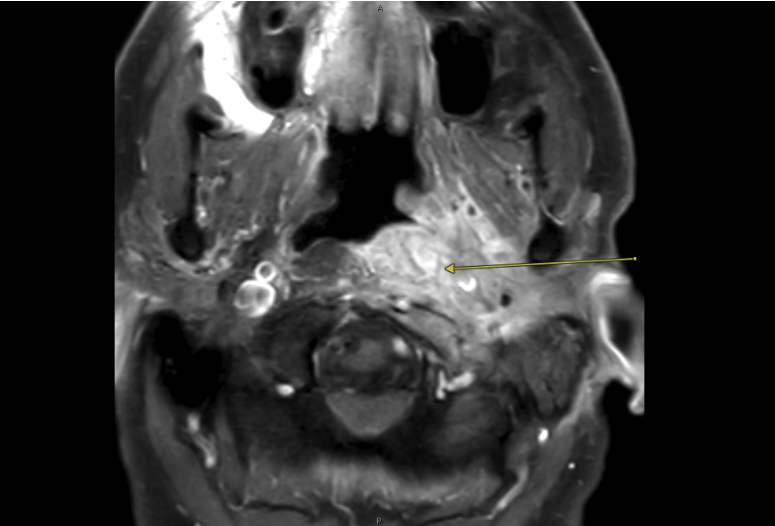

A man in his late 70s was referred to Carlos Pinheiro Neto, MD, PhD, endoscopic skull base surgeon and vice chair of otolaryngology—head and neck surgery at NYU Langone Health, for urgent, advanced management of complex skull base osteomyelitis. The infection involved the nasopharynx, clivus, petroclival junction, and petrous apex on the left side and also impacted multiple cranial nerves, resulting in dysarthria, dysphagia, and intense pain, with rapid deterioration of his overall condition.

MRI showing the extensive skull base infection (arrow). Source: NYU Langone Health.